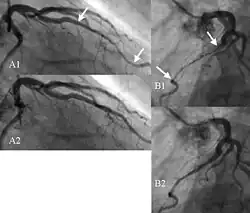

| Angiogram showing myocardial bridging resulting in arterial compression. | |